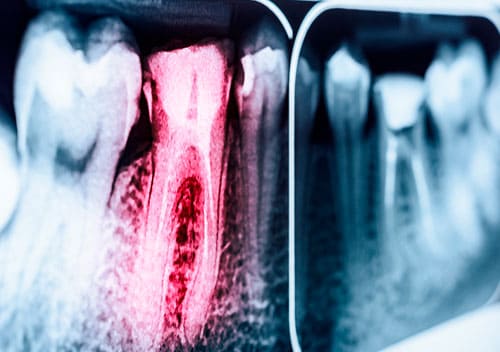

La endodoncia es la eliminación del tejido pulpar inflamado o infectado del interior de la cámara pulpar y de los conductos radiculares, rellenándolos herméticamente con un material que permita conservar el diente manteniendo su función. Este tratamiento de endodoncia es lo que comúnmente llamamos “matar el nervio”. La realización de este tratamiento es de vital importancia, ya que de lo contrario puede causar un dolor muy intenso e incluso infecciones del tejido blando llegando a producir abscesos o fístulas.

Las caries, infecciones o irritación en nervios suelen ser las causas que provocan dolor de muelas. Las caries producen orificios en la superficie del diente haciendo que el nervio quede expuesto y en algunas ocasiones se tiene que matar el nervio para que no produzca dolor. Lo más importante es acudir a un endodoncista profesional en Benalmádena lo antes posible para que sea revisado y que el tratamiento se ponga en marcha lo más pronto posible.